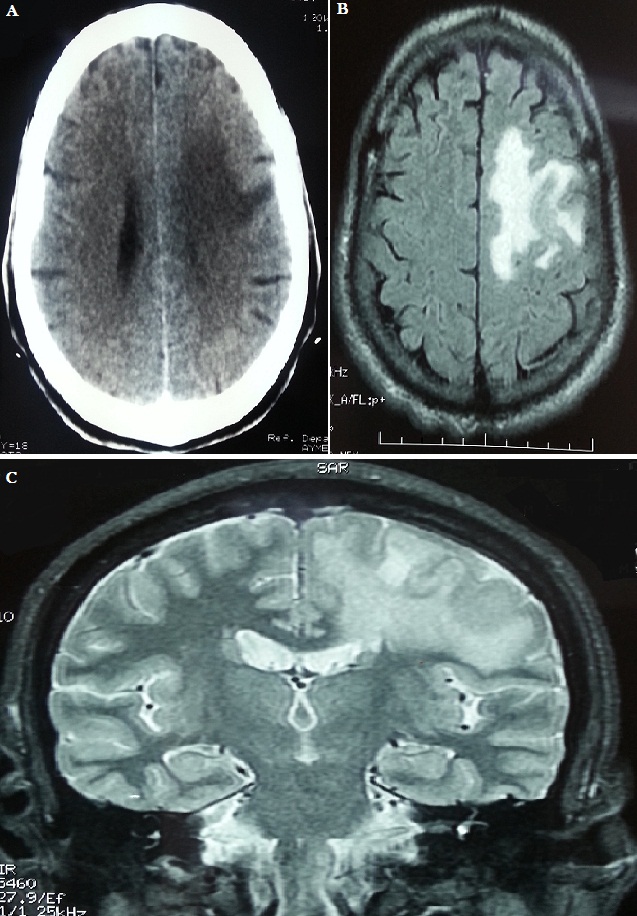

Cerebral tuberculomas are a rare and serious form of tuberculosis due to the haematogenous spread of Mycobacterium Tuberculosis. Symptoms and radiologic features are nonspecific, leading sometimes to misdiagnosis. We report the case of a 60-year-old male, with a history of diffuse bilateral infiltrative pulmonary disease at the stage of fibrosis, he made two generalized seizures associated with occipital headaches. CT scan showed a left frontal tumor, calcified lesion with edema around it. The patient was put under Depakine and corticosteroids. The evolution is marked by the occurrence of new seizures associated with heaviness of the right arm. Brain MRI showed a left posterior peripheral frontal meningioma with intralesional bleeding and significant edema around it with mass effect on the ipsilateral lateral ventricle. The patient was operated and the tumor was removed. In postoperative there was a Broca's aphasia with right hemiplegia. Pathological anatomical examination of the surgical specimen found a cerebromeningeal Granuloma with caseous necrosis in its pseudo tumor presentation (tuberculoma). The thoraco abdominal scan did not show any other tuberculosis lesions. The patient started antituberculosis treatment with 4 drugs (HRZE) for 2 months, followed by maintenance therapy (HR).The evolution was marked by the persistence of a right hemiplegia with Broca's aphasia. The patient was brought out in a wheelchair with functional rehabilitation sessions.